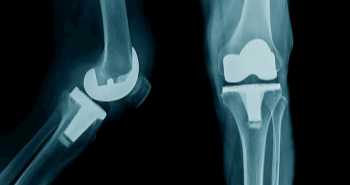

Ефективність та безпеку однократного передопераційного внутрішньовенного введення високих доз дексаметазону порівняли з двома еквівалентними побрібненими дозами периопераційно у рандомізованому проспективному плацебо-контрольованому подвійному сліпому дослідженні. Оцінювали зниження болю і поліпшення функції після тотального ендопротезування кульшового суглоба.

У дослідження було включено 165 пацієнтів з діагнозом остеоартрит кульшового суглоба, та яким було призначено первинне планове тотальне ендопротезування кульшового суглоба. Учасники були рандомізовані в три когорти: 1). група A (плацебо), яка отримувала 2 ін'єкції фізіологічного розчину периопераційно (n = 55); 2). група B, яка отримувала одноразову передопераційну дозу 20 мг дексаметазону і післяопераційну ін'єкцію фізіологічного розчину (n = 55); 3). група C, яка отримувала 2 дози дексаметазону 10 мг периопераційно (n = 55).